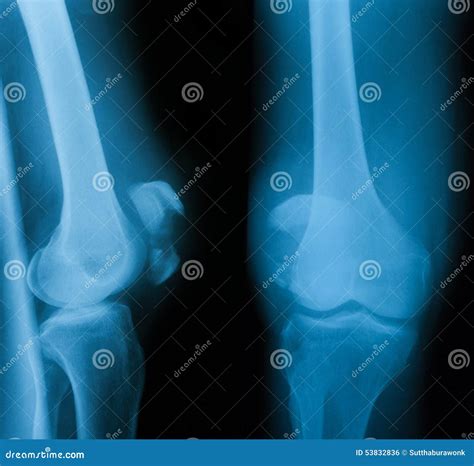

Radiologists Debate If The Knee Joint Lateral View Is Always Accurate

Knee Joint X-ray (AP And LATERAL) View Fracture And Displacement Of The ...